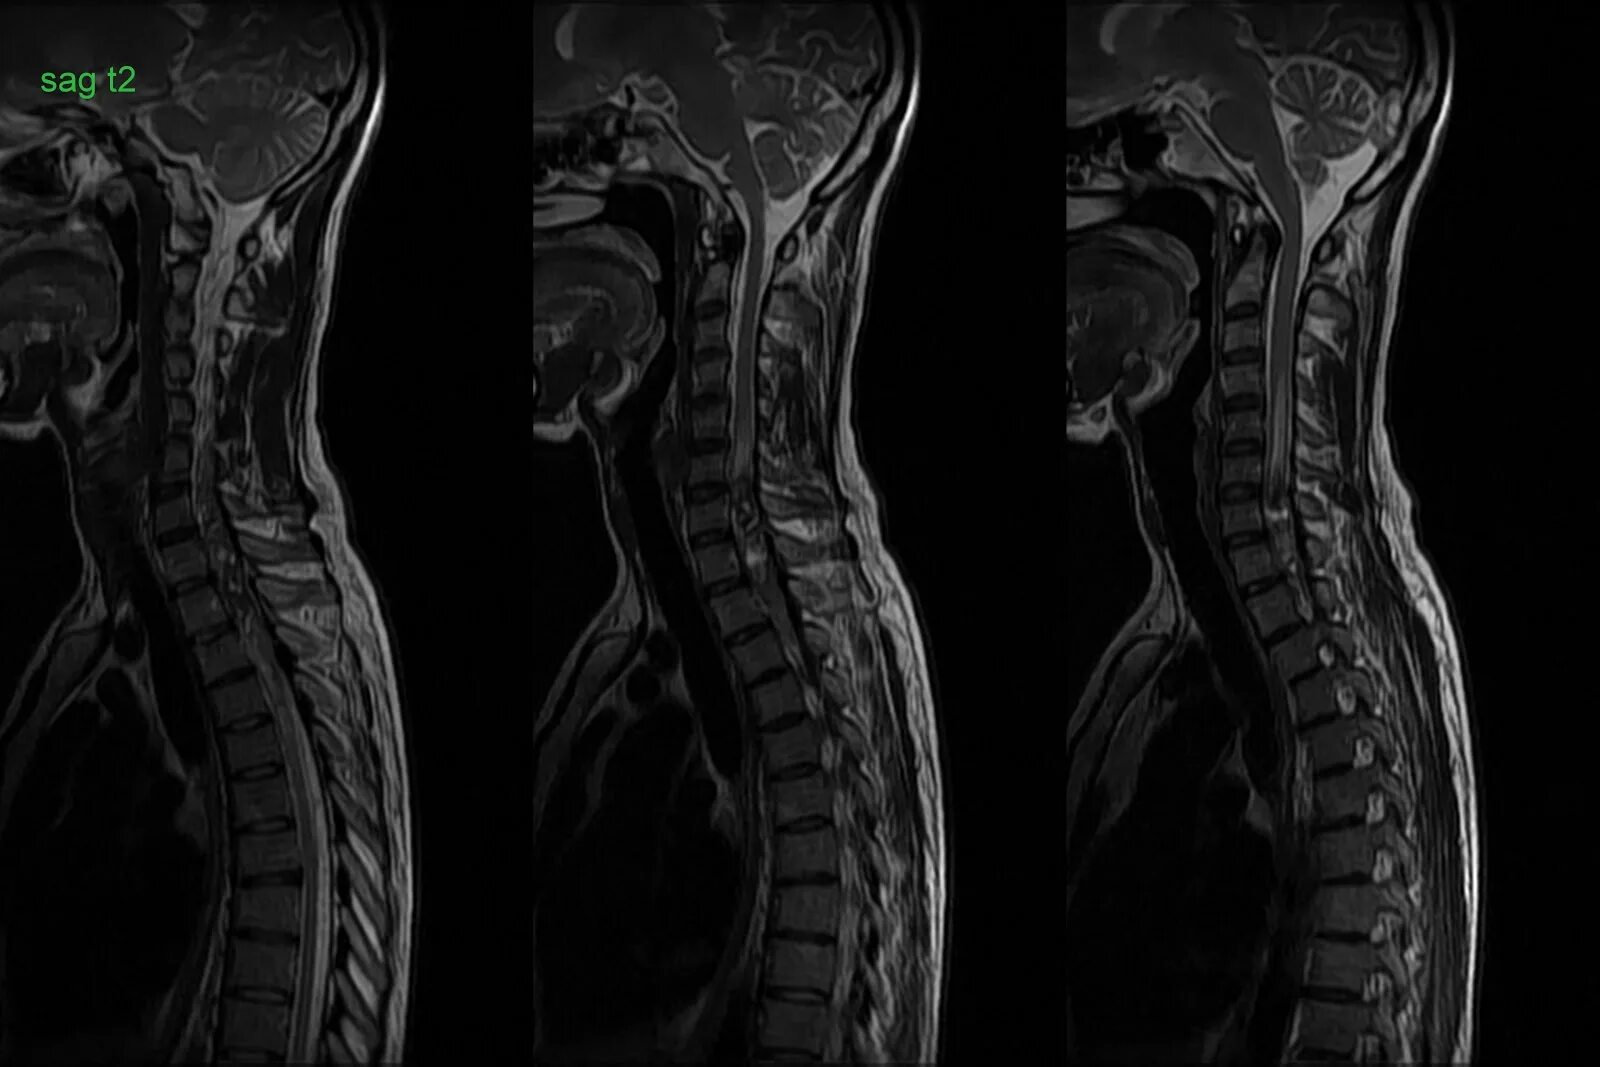

Spine mri